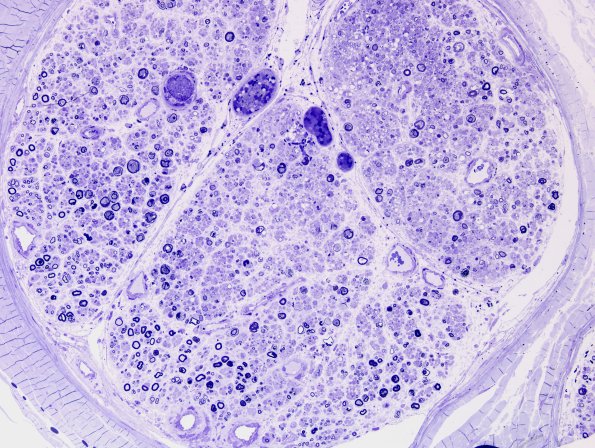

Washington University Experience | PERIPHERAL NEUROPATHY | 5 AXONAL REGENERATION | 3A1 SLE (Case 1) Plastic 2.jpg

3A1-3 In this case a patient with systemic lupus erythematosus developed microthrombi in multiple endoneurial vessels with resultant local axonal degeneration. The process in this patient produced numerous regenerative and degenerative pathology involving a small area of the endoneurium with numerous examples of pathology described here in detail. In most neuropathies ongoing active regeneration with growth cones is typically rare (see later 11-12 series in this album). (electron micrographs)